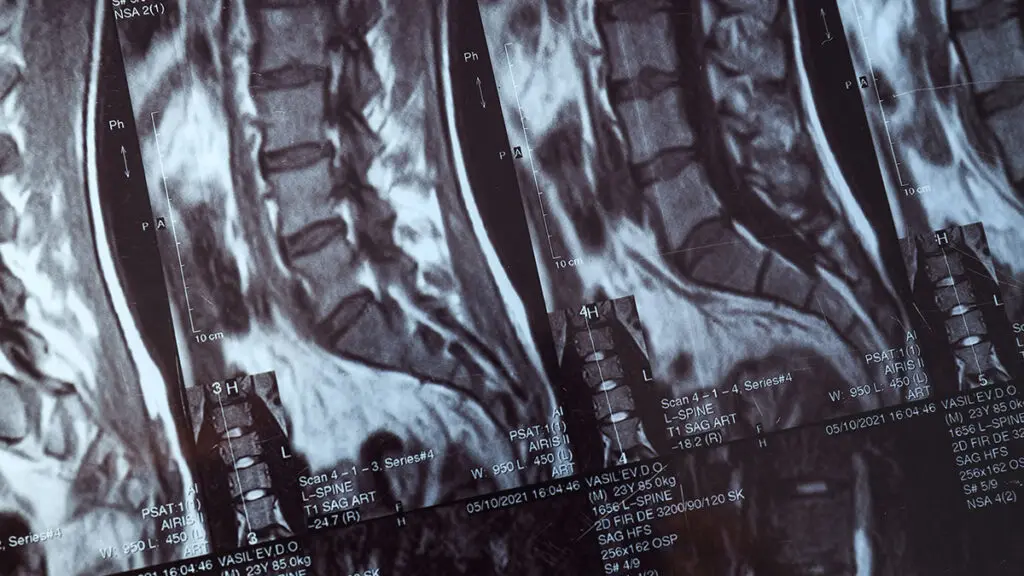

La microchirurgia ernia del disco è una delle procedure neurochirurgiche mininvasive più eseguite al mondo per il trattamento dell'ernia del disco sintomatica. Global Spine Solutions offre a Roma percorsi completi per microchirurgia ernia del disco: dalla diagnosi strumentale accurata alla pianificazione pre-operatoria, fino all'intervento vero e proprio e alla riabilitazione post-operatoria.